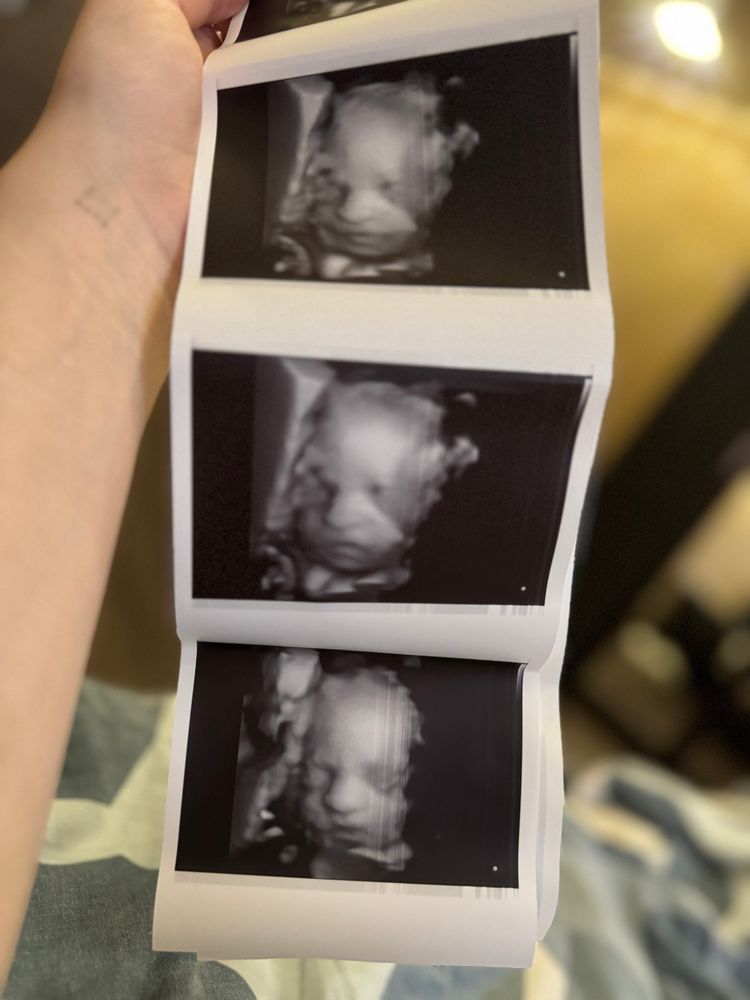

Девочки всем привет. Нет сил моих больше беременность 27 недель, первая долгожданная, все анализы в норме, в том числе узи и скрининг крови. Результаты хромосомных отклонения низкие. В 25 недель ездили с мужем на 3д/4д узи, на фото мне показался очень странный нос, в интернете смотрю 3д фотки других малышей и у всех носики курносые, а у нашего острый. Очень переживаю что это отклонение. Но утешаю себя тем что у меня тоже острая форма носа и он сам по себе не большой. Девочки выручайте у кого было что то подобное. Очень переживаю🥺

Не забывайте, что фото через воды делается, себя снимите через аквариум 🤣 А вообще, черты приблизительные, как по мне. Я 3д делала только с третьей дочкой, не похожи фото и результат)))

У знакомых смотрела фото с УЗИ, прям инопланетяне, носатые, губастые, жесть. А рождались с ангельской внешностью, сроду не подумаешь, что на фото тот самый малыш. 3D снимки такая условность. Сквозь воды и ткани очень искажается вид. Мне на 2 скрининге сфоткали, нос тонкий как спичка и длинный, у нас с мужем хорошие носы, не армянские и не тонкие, так что не ориентируйтесь особо на фото)

Так 3д узи это же не фотка малыша , а проекция отражения ультразвука , отличный у вас носик